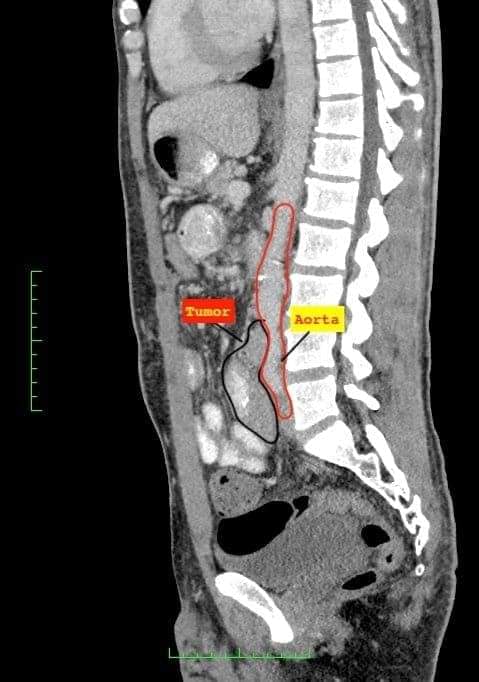

في عملية نوعية في الخدمات الطبيه الملكية، قام فريق طبي بمدينة الحسين الطبية مكون من أطباء الجراحة العامة والأورام وأطباء جراحة الأوعية الدموية والشرايين باستئصال كامل لورم ليفي نادر من الأمعاء في عملية جراحية اشتملت على استئصال واستبدال الشريان الأبهري البطني نتيجة امتداد الورم الى داخل جدار الشريان .

وفي التفاصيل ذكر العقيد الطبيب سهم القسوس مستشار الجراحة العامة وجراحة الكبد والأورام أن هذا الورم يصيب ما نسبته اقل من شخص من كل مليوني شخص، مبينا أن الورم كان مسببا لانسداد جزئي في الأمعاء، وأن عملية الاستئصال الكامل في هذه الحالة المتقدمة ليست ممكنه بدون استئصال الشريان الأبهري الرئيسي، بتشاركية مع أطباء جراحة الأوعية الدموية والشرايين.

وقال العقيد الطبيب جان الشيشاني مستشار جراحة الأوعية الدموية والشرايين أن امتداد هذا الورم الى داخل جدار الشريان وعدم استئصاله يؤدي في النهاية إلى نزيف شديد ووفاة المريض، مما شكل دافعآ رئيسياً اضافياً لاستئصال هذا الورم والشريان الرئيسي الأبهري، وان هذا الإمتداد نادرا جداً، وانه لا يوجد سوى عدد محدود من الحالات المشابهة المنشورة عالمياً .

وأشار المقدم الطبيب محمد الرشايدة مستشار جراحة الأوعية الدموية والشرايين أن الصور الطبقية وفحوصات الأنسجة التي تمت بعد إجراء العملية بينت الاستئصال الكامل للورم، و أن المريض ستتم متابعة حالته المرضية بشكل دوري بعد ان تماثل للشفاء و غادر المستشفى بصحة جيدة.